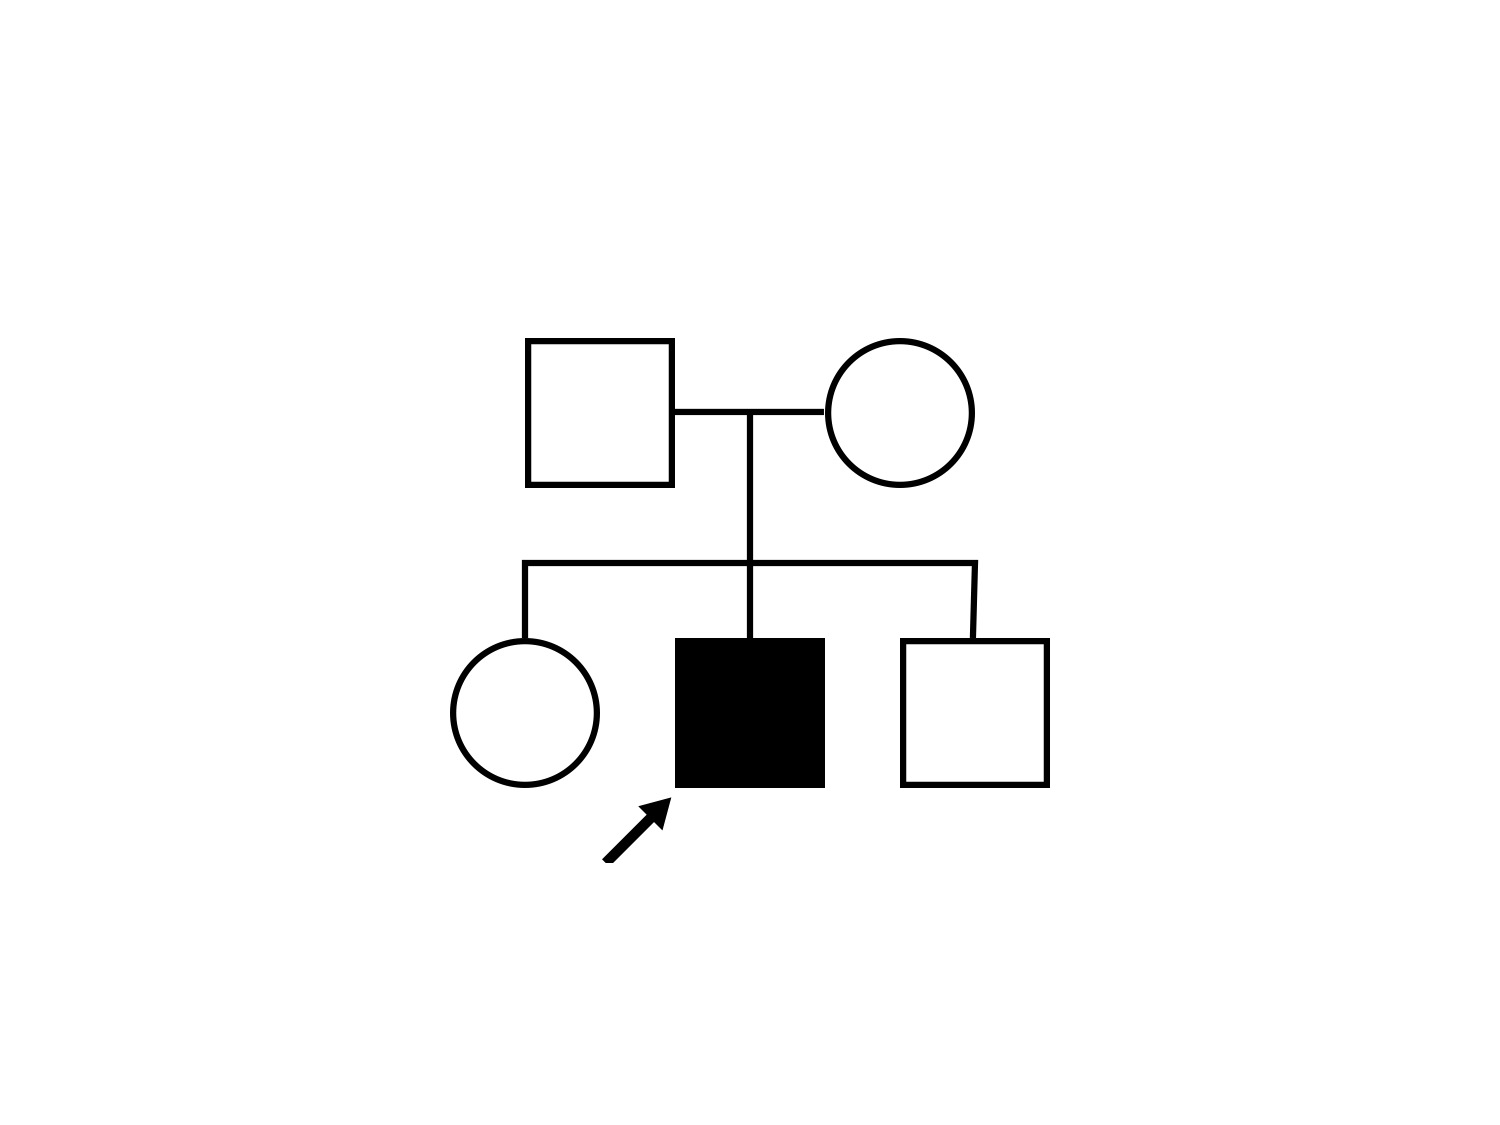

| Neurofibromatosis | NF2 | Trp258 del1tG | AD |